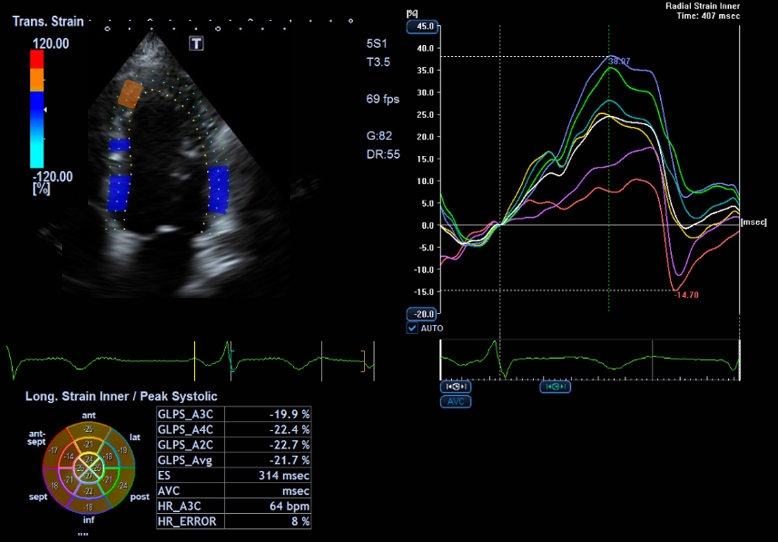

Auto-EF with Global Longitudinal Strain (GLS)1

- Automatic integration of Strain measurements with Ejection Fraction and volume measurements

- No need to enter dedicated strain packages

- Aplio systems automatically calculate Ejection Fraction, LV volumes and now GLS.

- Auto EF with Full-assist function is powered by artificial intelligence2

1Available on Aplio i-series / Prism Edition and a-series

2Available on Aplio i-series / Prism Edition

Automatic integration of Strain measurements with Ejection Fraction and volume measurements without the need of dedicated strain packages.